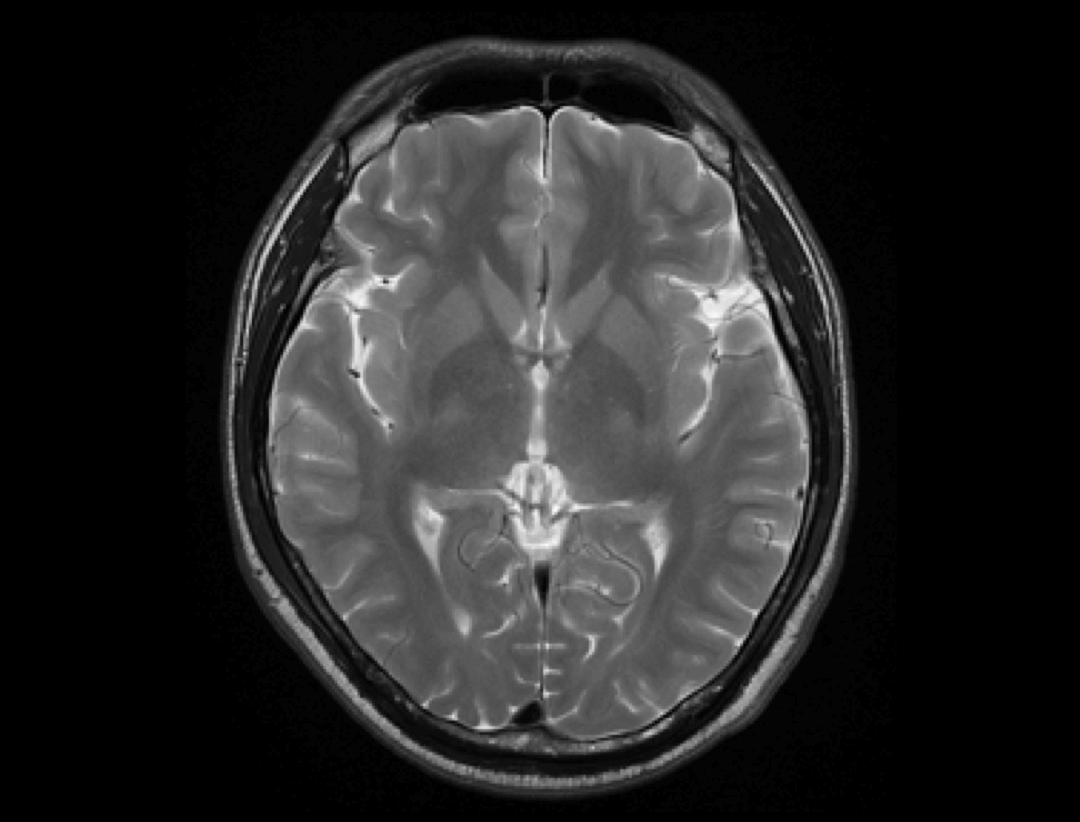

Imagistică neuro multi-parametrică

După achiziție pot fi generate hărți parametrice precum FA, RA, ADC și FA color, care reflectă viteza și direcția mișcării apei în țesuturi. Această tehnică oferă informații precise pentru diagnosticarea bolilor neurologice, precum leziunile de substanță albă.

Neuro